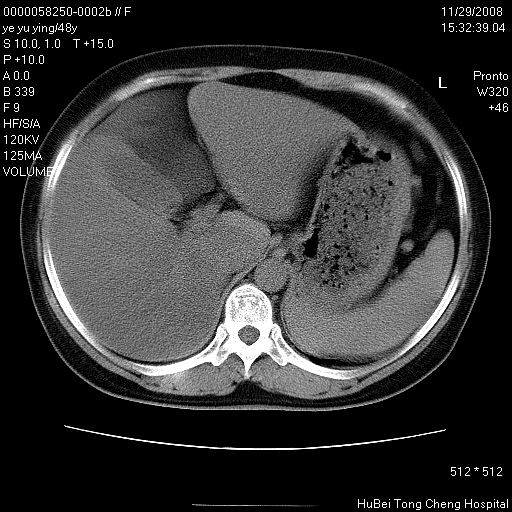

以下是引用zsl6918在2008-11-29 21:47:00的发言:[br]恶性肿瘤病史,转移瘤首先考虑。脂肪肝,胆囊结石。

以下是引用huenhao在2008-11-29 22:11:00的发言:[br]脂肪肝,胆囊结石。左肺病灶建议定期复查。

以下是引用liuyue在2008-11-30 5:44:00的发言:[br]1.左肺病变,首先考虑感染性病变,转移待排;建议治疗后复查。[br]2.肝脏密度普遍减低,考虑与化疗有关。[br]3.胆囊结石.